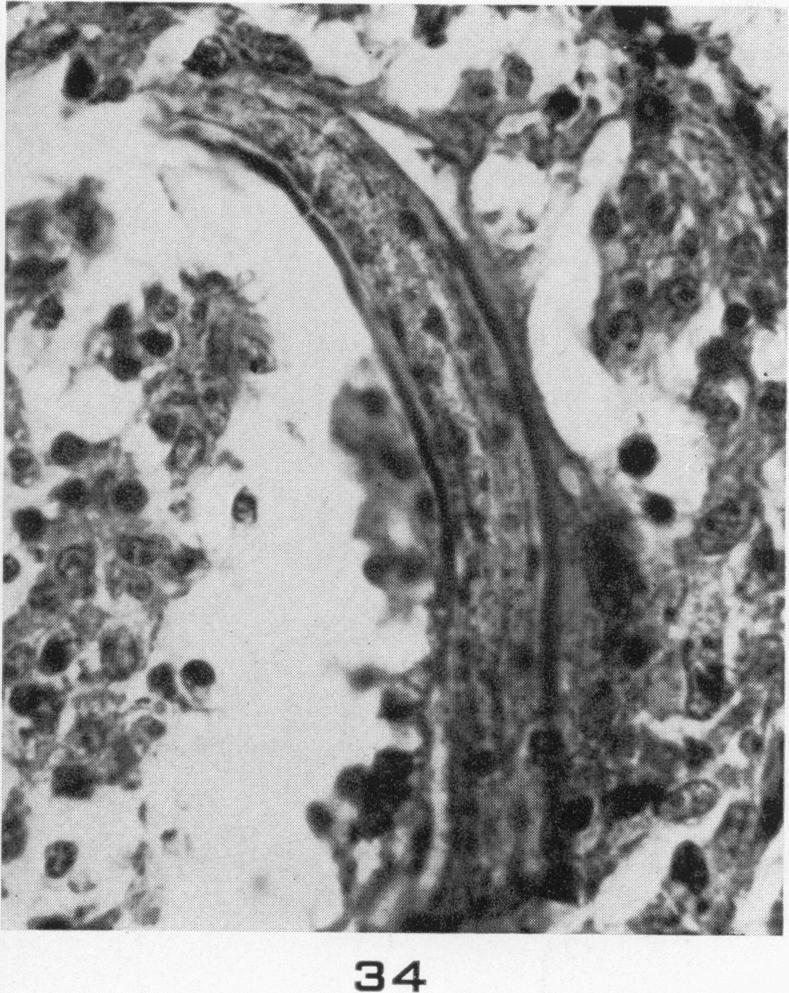

Visceral larva migrans; with a case report.

Am J Pathol. 1956 Jul-Aug;32(4):777-803.